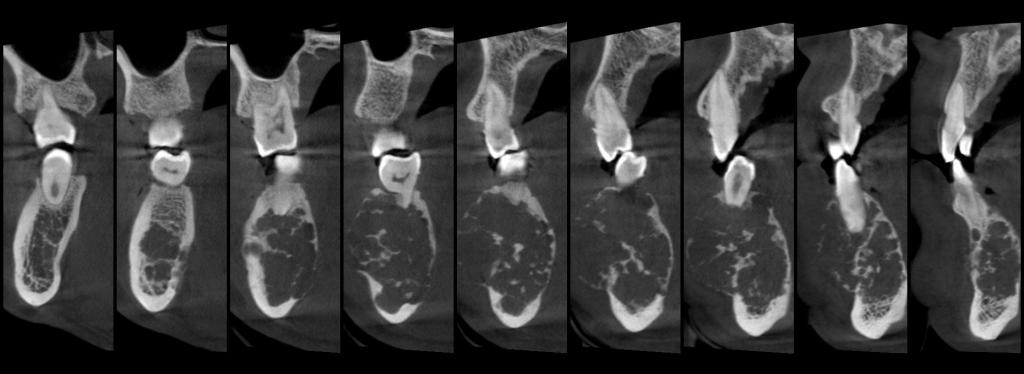

常规开展:数字化根尖片/横断牙合片、数字化口腔曲面体层片、头影测量侧位/正位片、手腕骨片、颅颌面CBCT、牙齿CBCT的检查以及涎腺造影、窦道 瘘管造影。

颅颌面CBCT

诊断范围涉及牙体牙髓病、牙周病、阻生牙/多生牙定位、种植牙术前CT评估分析、颞下颌关节CT诊断分析、,颌骨及涎腺疾病、颌面发育畸形、正畸治疗辅助诊断等大部分颌面部疾病,为临床医疗提供强有力的支持。